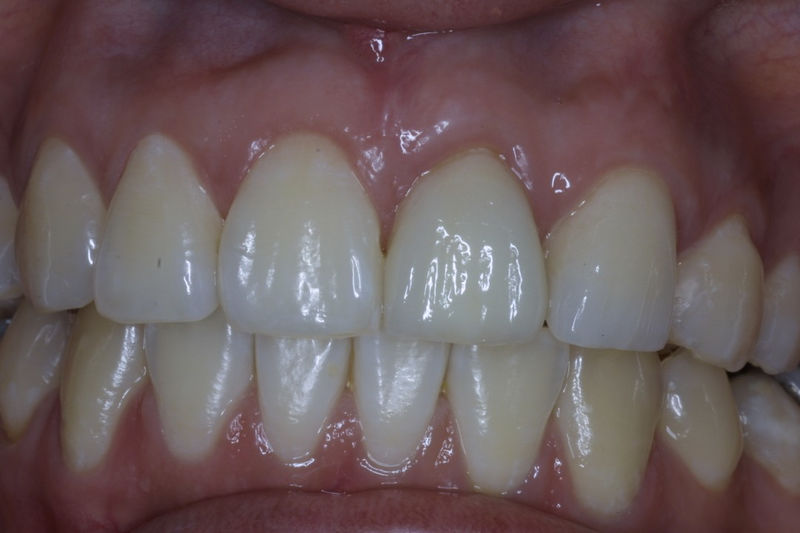

Amplia gama de tratamientos para mejorar la apariencia de la sonrisa, corrigiendo el color, la forma, el tamaño, la alineación y la posición de los dientes. Los procedimientos más comunes y solicitados incluyen el blanqueamiento dental, las carillas y coronas, así como las resinas.

Son restauraciones que cubren toda la cara frontal del diente, generalmente empleadas en el sector anterior y cuya finalidad es primariamente estética.

Restauraciones fabricadas en el laboratorio con materiales estéticos, los cuales cubren de manera total dientes anteriores y posteriores. Se utilizan primariamente para restaurar dientes con caries, fracturas y/o defectos amplios, así como soportes de puentes. Para poder enviar el caso al laboratorio se toman impresiones utilizando materiales de impresión o técnicas modernas digitales.